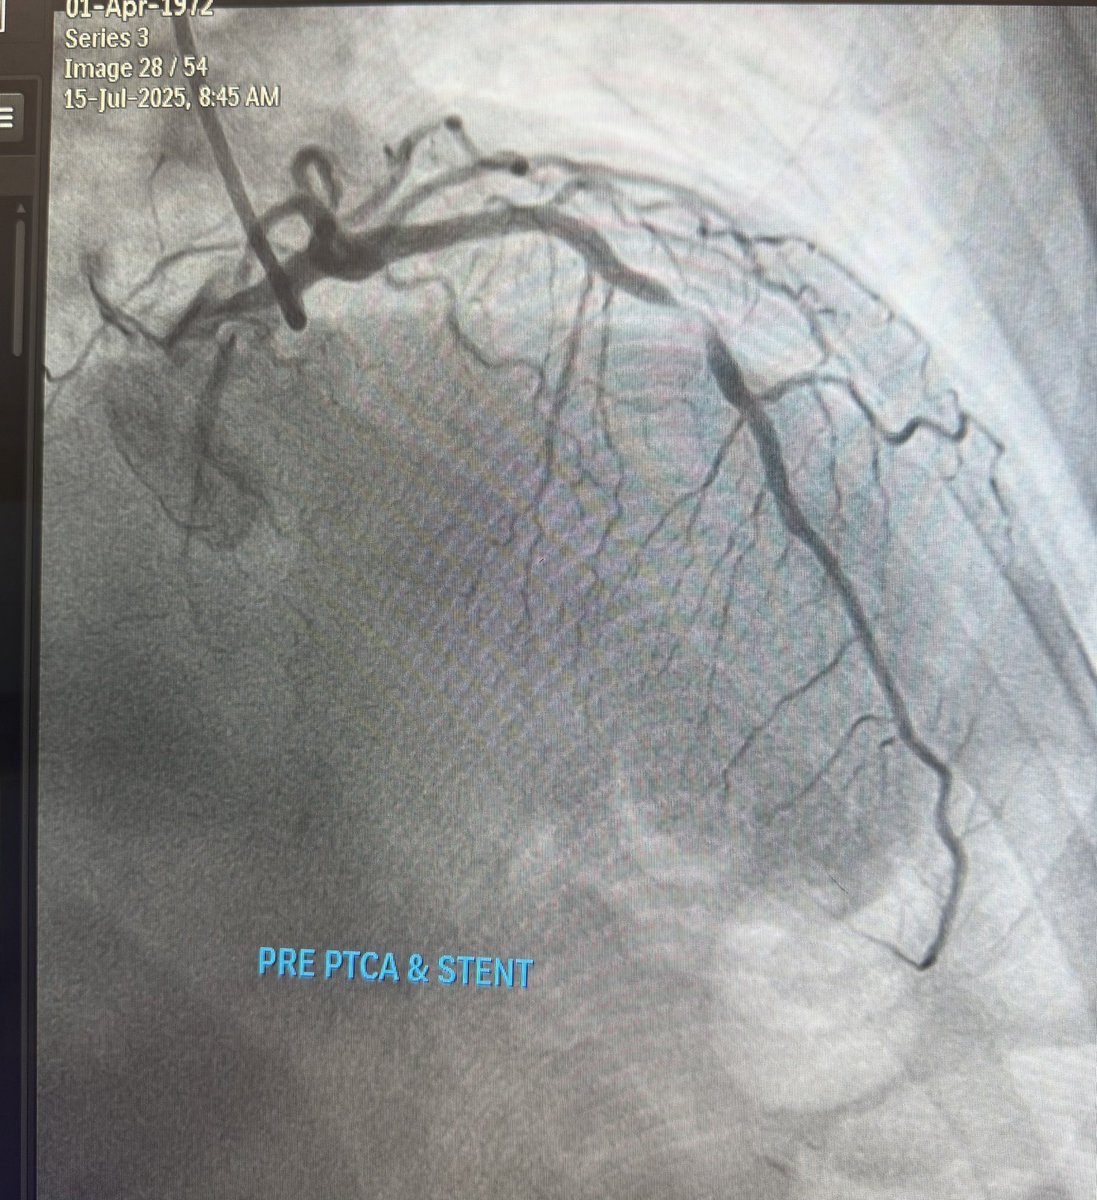

58 yo male,NSTemi...what would be your approach??Yoshinobu Murasato FRANCESCO BURZOTTA Ahmed Kamel,MD,FESC,FSCAI . Mamas A. Mamas European Bifurcation Club Giuseppe Biondi-Zoccai European Bifurcation Club Aliyor GANIEV, MD Alloune Imed eddine Evandro Martins F. MD jedicath աǟզǟʀ.ǟɦʍɛɖ MIЯVΛƬ #IC Pr Rania HAMMAMI Lorenzo Azzalini pierredeharo billel abboub Tsutomu Fujita MD #cardio

Mid 60s F, normal EF, no VHD, A1c 7.5-8, low-level NSTEMI, CC=chest pain. Isolated LM bifurcation 1,1,1. CABG, Provisional, DKC/nanocrush, LM provisional + DCB LCX? Sripal Bangalore Dr Shariq Shamim Jeffrey Wilson, MD Aliyor GANIEV, MD Dr Imran Hanif Hashmi Dr Why Less-Is-More Cardiologist Jack Hall